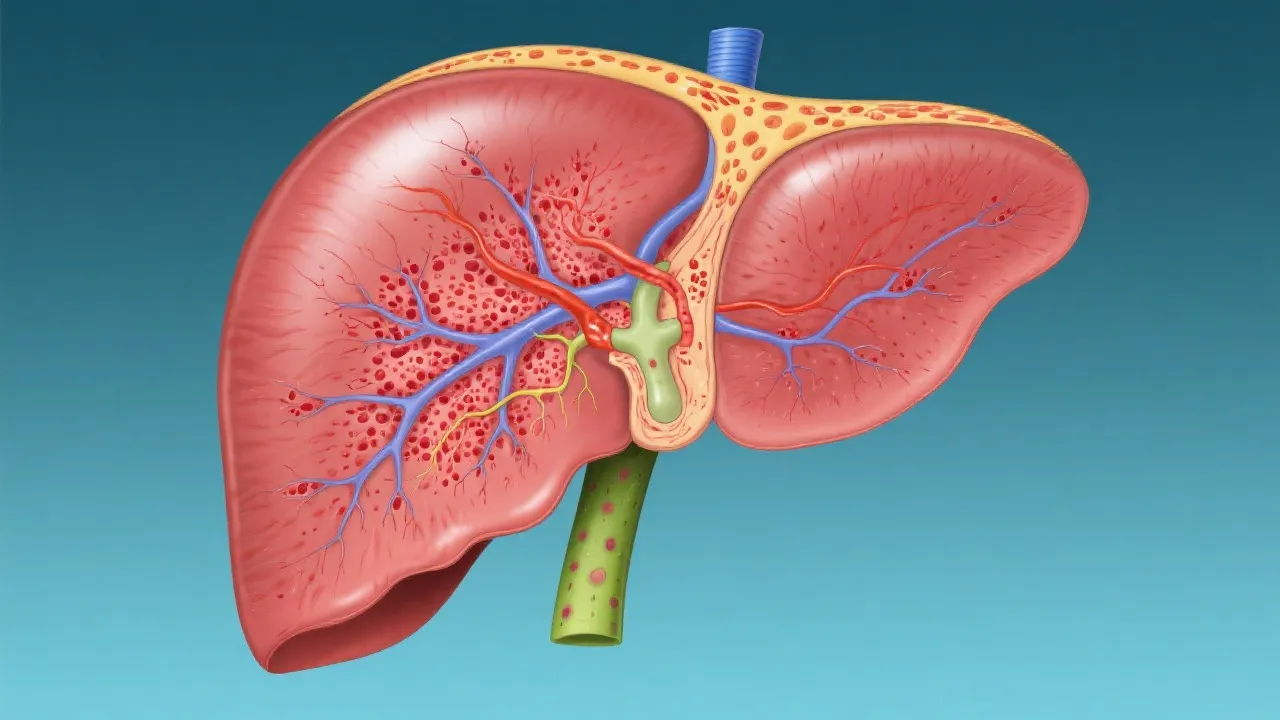

Hepatitis, in general, refers to the inflammation of the liver and can arise from various causes, including viral infections, autoimmune responses, toxic substances, and heavy alcohol use. Each type of hepatitis presents its challenges, requiring tailored approaches in diagnosis and management. The liver is essential for metabolism and detoxification; when inflamed due to hepatitis, it can lead to significant health issues, including liver cirrhosis and carcinoma. Hepatitis can affect individuals differently, depending on factors like age, sex, genetic predisposition, and overall health. Understanding these differences is vital for effective treatment and management strategies for each subtype.

The pathophysiology of Seimc Hepatitis involves complex interactions between the immune system and liver cells, resulting in inflammation and hepatocyte damage. The immune response may result in either a direct attack on liver cells or an exaggerated inflammatory response that causes collateral damage. This distinction is crucial, as therapies may focus on modulating the immune response or addressing the underlying triggers to prevent further liver damage.

Furthermore, inflammation can lead to a cascade effect within the liver, initiating fibrosis. If not managed appropriately, this process can evolve to severe complications such as cirrhosis and hepatocellular carcinoma, thereby underscoring the importance of early diagnosis and intervention in managing Seimc Hepatitis.

Diagnosing Seimc Hepatitis involves a multifaceted approach, including a patient's clinical history, biochemical tests, and advanced imaging techniques. Liver function tests are pivotal in revealing inflammation levels, while imaging assists in structural assessments. Blood tests can indicate elevated liver enzymes, which suggest inflammation or damage to hepatocytes. Additionally, more specific tests aimed at identifying potential autoimmune markers may aid in the consideration of Seimc Hepatitis as a diagnosis.

In some cases, a liver biopsy may be warranted to provide a definitive diagnosis through histological examination. This step can give insight into the extent of liver damage and inflammation, guiding treatment strategies. Advanced imaging techniques, such as MRI and CT scans, can visualize liver architecture and identify abnormalities or complications that may accompany Seimc Hepatitis.